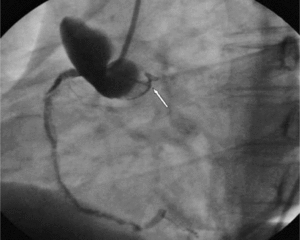

Szczególną grupę chorych stanowią ci z jatrogennym AAS. W populacji tej dominują ostre rozwarstwienia z wrotami dyssekcji w aorcie wstępującej. Najczęstszymi przyczynami jatrogennego AD są zabiegi cewnikowania serca (ryc. 2) oraz operacje na zastawce aortalnej [8]. Innym potencjalnym zagrożeniem jest leczenie kontrapulsacją wewnątrzaortalną. Jatrogenne rozwarstwienie aorty wiąże się z większą śmiertelnością niż niejatrogenne (35 vs 24%) [9], ponieważ częściej obejmuje ujście tętnic wieńcowych lub naczyń dogłowowych, a sama dyssekcja postępuje gwałtownie.